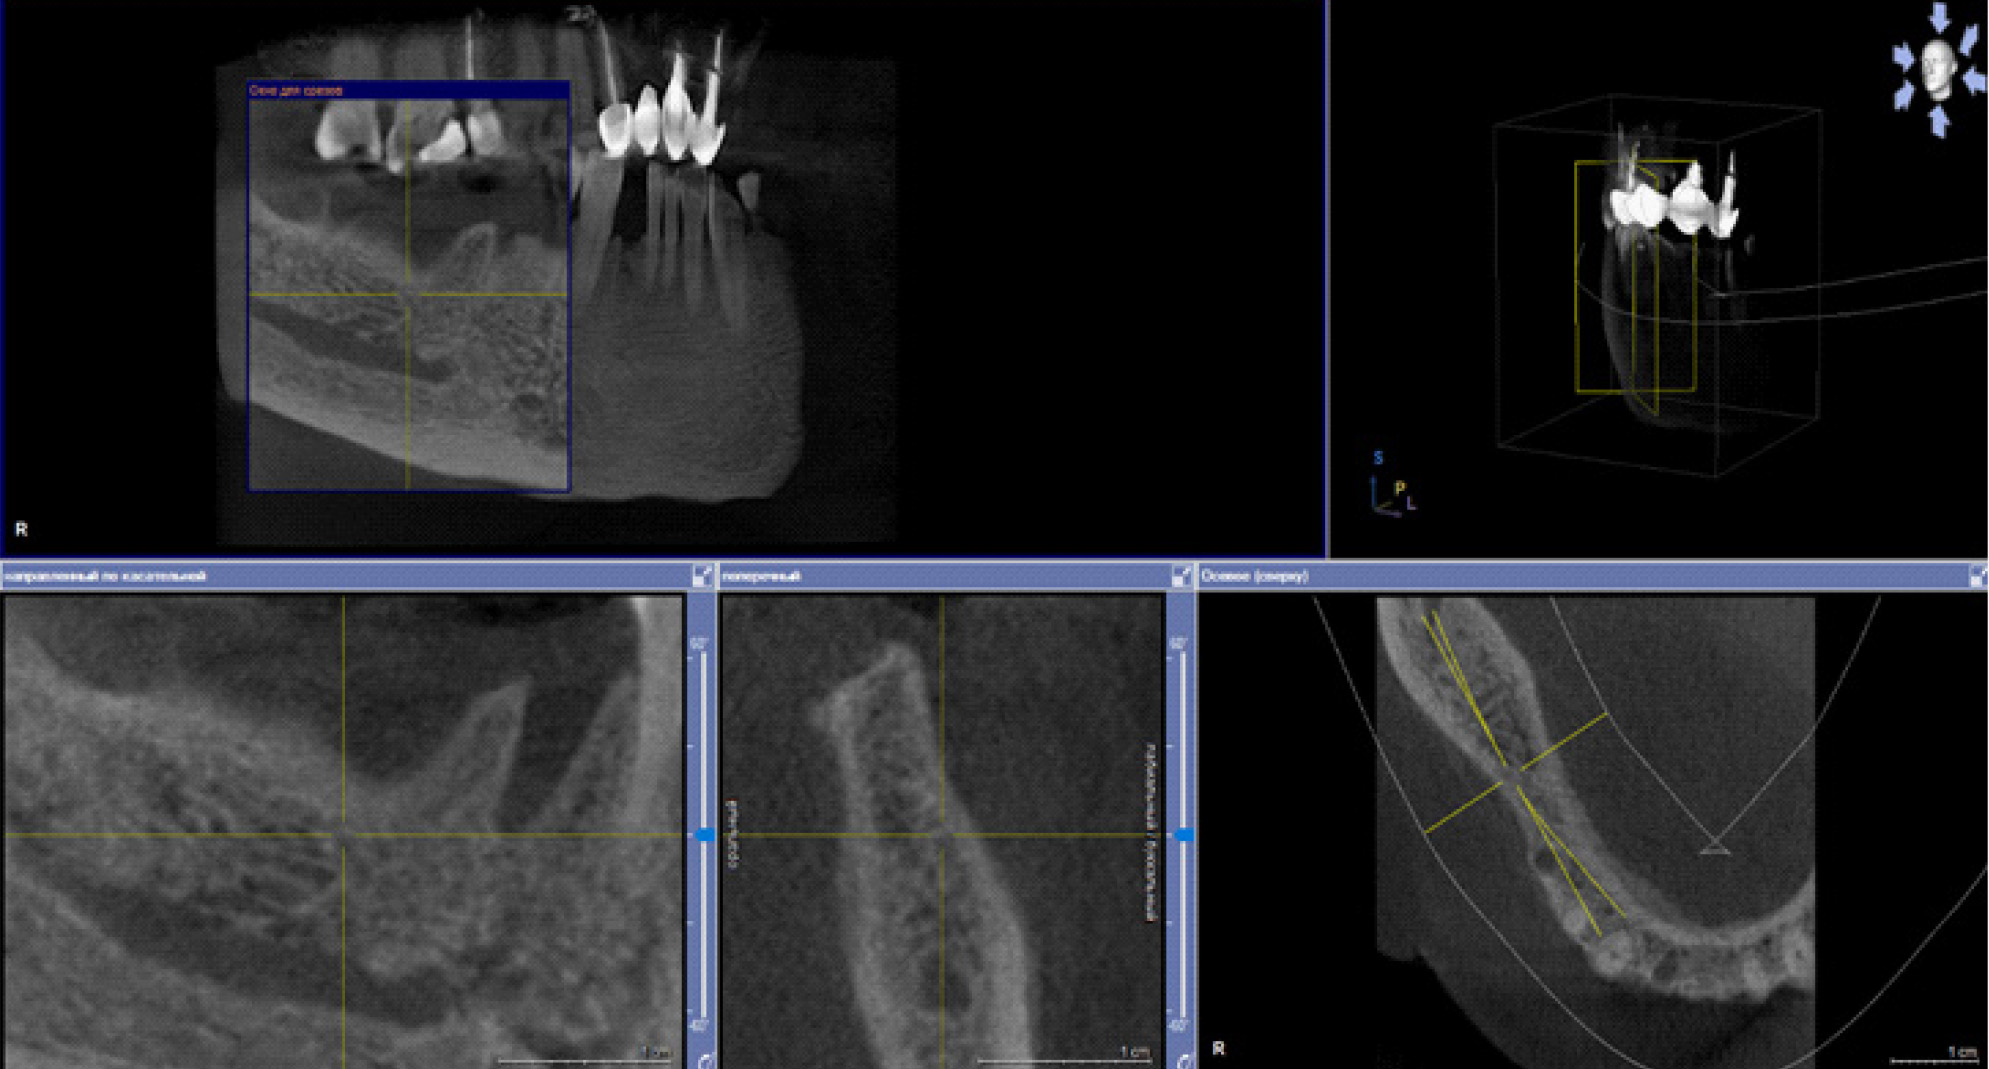

В настоящее время выделяют два основных подхода к лечению БФОНЧ, к ним относятся консервативный и хирургический подход. Выбор тактики лечения пациента зависит от стадии заболевания. Консервативное лечение предусматривает назначение пациентам курсовой антибактериальной, симптоматической терапии препаратов для улучшения микроциркуляции, ежедневной обработки очагов поражения костной ткани растворами антисептиков, частичная некроэктомия, удаление подвижных секвестров, а также тщательное соблюдение гигиены полости рта (рис. 4).

Рис. 4. Компьютерно-томографическое исследование на этапе лечения остеонекроза нижней челюсти справа у пациентки Б. в 2023 г.

За период лечения пациентки Б. было выполнено хирургическое лечение в следующем объеме: кюретаж лунок удаленных зубов, частичная секвестрэктомия, резекция альвеолярной части нижней челюсти справа, вскрытие и дренирование гнойных очагов в стадии обострения патологического процесса. Отмечалось улучшение клинической и рентгенологической картины в полости рта (рис. 5, 6).

Рис. 5. Клинические проявления бисфосфонатного остеонекроза нижней челюсти справа у пациентки Б. в 2024 году

Рис. 6. Ортопантомограмма на этапе лечения остеонекроза нижней челюсти справа у пациентки Б. в 2024 г.